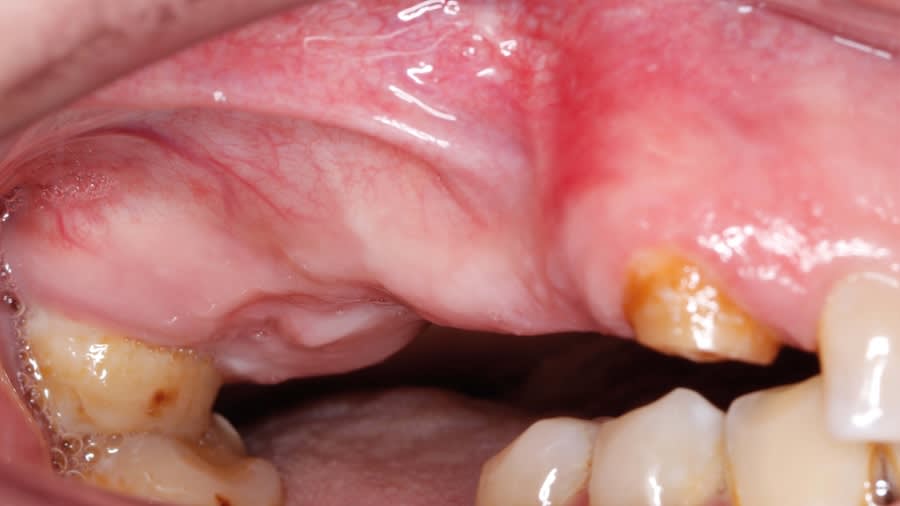

Case 1 (Figure 3 through Figure 24) depicts a 3-year follow-up of combined osseodensification sinus protocol IV in a severely resorbed maxillary ridge with ≤0.5 mm bone height in molar sites and horizontal deficiency at the first premolar site, using a two-stage approach for implant placement.

Case 2 (Figure 25 through Figure 36) illustrates a 3-year follow-up of the osseodensification sinus protocol IV in a severely resorbed right maxillary ridge with <0.5 mm bone height in molar sites, using a two-stage approach for implant placement.

Case 3 (Figure 37 through 44) shows a case of significant trauma history with a 3-year follow-up of the osseodensification sinus protocol IV in a severely resorbed right maxillary ridge with ≤0.5 mm bone height in molar sites, using a two-stage approach for implant placement.